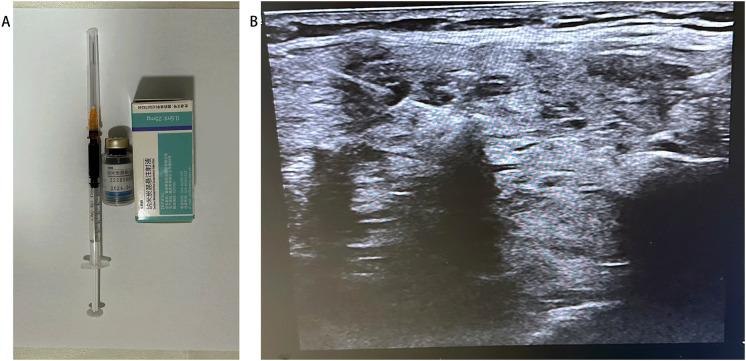

METHODS

BMNG patients who previously underwent thyroidectomy and received reoperation between January 2019 and January 2022 were retrospectively recruited. The Dunhill approach was employed for all patients. The patients were divided into two groups: the CNs group, who received injection CNs injection 1 hour before the operation (n = 24), and the control group, who underwent thyroid surgery without CNs injection (control group, n = 25). The numbers of PGs preserved , autotransplantation, the accidental removal of the PGs, and the parathyroid hormone level were recorded and analyzed.

回顾性招募2019年1月至2022年1月期间曾接受甲状腺切除术并接受再次手术的BMNG患者。所有患者均采用邓希尔手术方式。患者分为两组:CNs组,在手术前1小时接受CNs注射(n = 24);对照组,未接受CNs注射而进行甲状腺手术(对照组,n = 25)。记录并分析保留的PGs数量、自体移植情况、PGs的意外切除情况以及甲状旁腺激素水平。